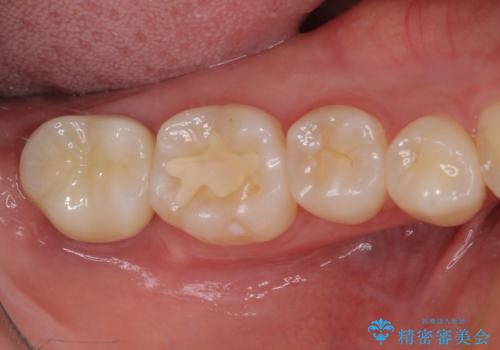

歯の高さが増したことで、かぶせものが外れにくくなったことはもちろん、今まで無理と言われていたセラミッククラウンも装着でき、さらには歯間部の清掃性も向上したため、患者様には大変満足していただけました。